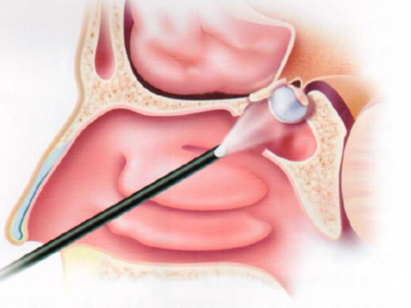

垂体瘤的治疗大多数的最佳方案为内镜经鼻手术。鼻腔属于耳鼻喉科范畴,术后需要耳鼻喉医生了解鼻腔粘膜修复情况,鼻腔是否通气、是否有鼻窦炎,是否有脑脊液漏,是否会头痛等情况。根据具体情况,耳鼻喉科医生会清理鼻腔、内镜观察、药物治疗,并制定下次复诊的时间。

垂体瘤手术主要由神经外科医生完成。术后复查,神经外科医生需要了解患者术后恢复情况、鼻腔改善情况、内分泌情况、视力视野恢复情况等。了解是否有残留、复发,并且决定下一次复查的时间。如果发现有复发,给出专业建议,观察、放疗还是再次手术治疗。